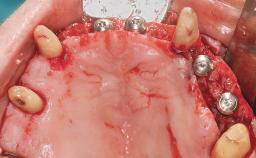

Immediate Loading of Eight Implants in the Maxilla and Six Implants in the Mandible and Final Restoration with Three-Unit and Four-Unit FDPs

Extensive scientific evidence has confirmed that immediately loaded implants with fixed full-arch provisional restorations can osseointegrate with success rates similar to conventionally or delayed loaded implants. A number of immediate-provisionalization techniques for edentulous jaws have been described. Some protocols differ when it comes to prefabricated provisional templates versus complete denture conversion; intrasurgical impressions versus direct relining; and cemented versus screw-retained provisional restorations. In this context, complete-denture conversion has been proposed for either intrasurgical impressions or direct relining. Another possibility is the utilization of a prefabricated provisional to be adapted either in the mouth (by direct relining) or in the laboratory (on a working model obtained from an intrasurgical impression).

# of Implants 14

Type of Implants One-Piece

Modality 6+ implants with immediate loading